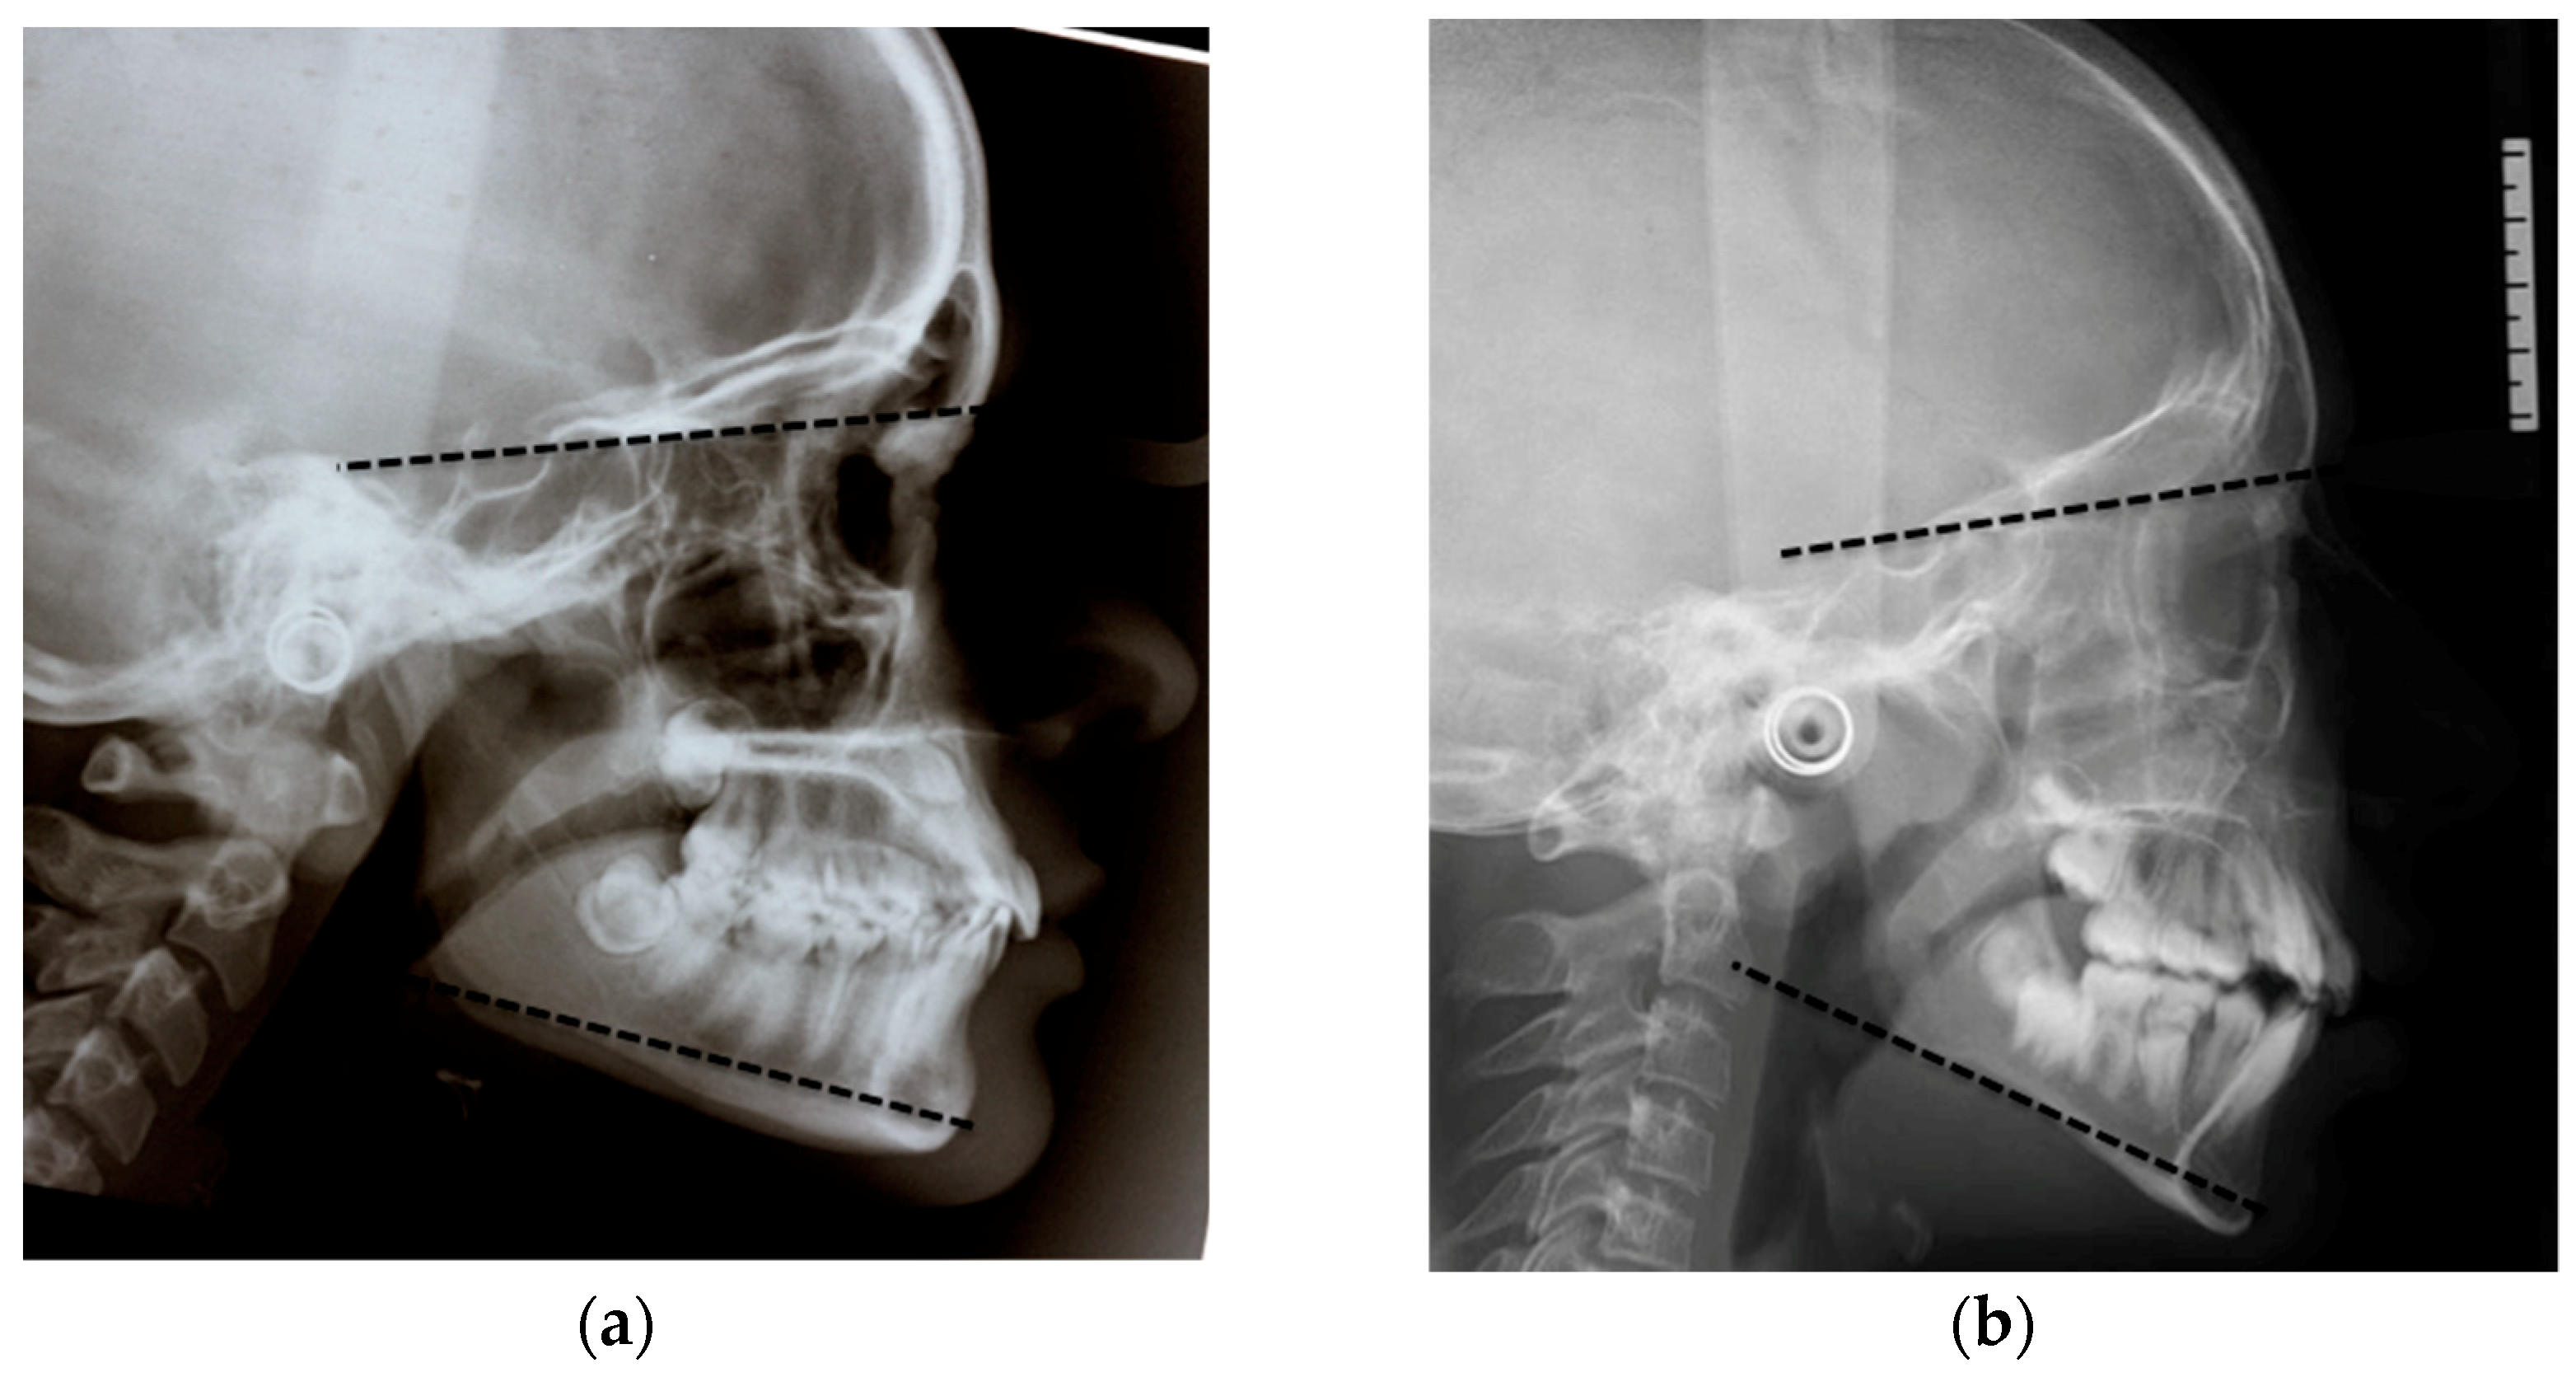

For this study, the cephalometric analysis was performed as shown in Figure 1a,b. Briefly, three cephalometric variables were assessed: the CoGoMe^ measured the mandibular structure, which is the angle between the condylar axis (Condylion-Gonion) and the mandibular base (Gonion-Menton); the SN^GoGn determined jaw divergence, which is the angle between the anterior cranial base (Sella-Nasion) and the mandibular plane (Gonion-Gnathion); and the ANPg^ assessed sagittal jaw discrepancy, which is the angle between the Nasion-point A line and the Nasion-Pogonion line [19].

The sagittal malocclusion was classified into three groups according to the ANPg^: Class III with an ANPg^ equal to or less than −1°, Class I with an ANPg^ between −1° and 5°, and Class II with an ANPg^ equal to or greater than 5°. Similarly, the sample was divided into three groups according to their vertical malocclusion: hypodivergent with an SN^GoGn equal to or less than 27°, normodivergent with an SN^GoGn between 27° and 37°, and hyperdivergent with a SN^GoGn equal to or greater than 37°, as seen Figure 2a–c.

Figure 1. (a) Cephalometric analysis and landmarks. Landmarks: A (Point A), most posterior point of the frontal concavity of the maxillary between the anterior nasal spine and the alveolar processes; N (Nasion), most anterior point of the junction of the nasal and frontal bone (frontonasal suture); S (Sella), centre of the hypophyseal fossa; Go (Gonion), midpoint of the curvature at the angle of the mandible; Co (Condylion) the highest and most posterior point on the contour of the mandibular condyle; Pg (pogonion), the most anterior point of the symphysis; Gn (Anatomical gnathion), point of the mandibular symphysis on the facial axis; and Me (Menton), most inferior point of the mandibular symphysis. (b) Reference: NA (Nasion-point A line) line through N and A; NPg (Nasion-Pogonion line) line through N and Pg; SN (Sella-Nasion line) line through S and N; GoGn (Mandibular plane) line through Go and Gn; CoGo (condylar axis) line through Co and Go; and GoMe (Mandibular base) line through Go and Me. Dentistry 07 00104 i001 SN^GoGn, Dentistry 07 00104 i002 CoGoMe^, Dentistry 07 00104 i003 ANPg^.

Figure 2. (a,b) Hypodivergent and hyperdivergent patients according to SN^GoGn; and (c) Normodivergent patient according to SN^GoGn.